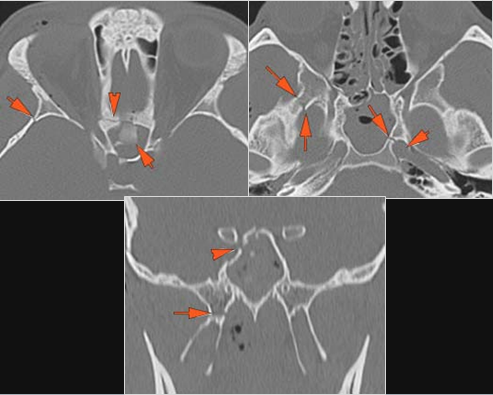

Possible facial, mandibular, orbital, and/or skull fractures, due to craniofacial trauma.Exam

Non-contrast CT of the maxillofacial region was obtained with 0.5-1.0 mm thick sections in the axial plane and reformatted 3D and/or in the coronal and sagittal planes and viewed interactively in 3 dimensions at the computer workstation.